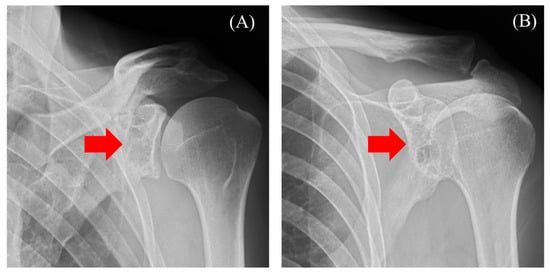

2.1. Case 1

2.2. Case 2